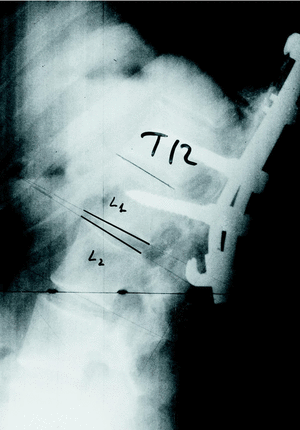

Para evaluar la deformidad en cifosis caudal a la instrumentación, se midió el valor angular del DFI (primer espacio libre por debajo de la instrumentación, asignando valores negativos a los espacios en cifosis) que fue de 8,9° (mínimo: 1 y máximo: 15°) en preoperatorio, 4,4° (mínimo: 0 y máximo: 10°) en postoperatorio y 2,1° (mínimo: 8 y máximo: 8°) en la medición final. Ello supuso una disminución de lordosis de 6,8°. En 5 casos el DFI se cifosó, sin que hubiera diferencias entre el grupo de vía posterior y el grupo de doble vía. En todos ellos la instrumentación distal no llegó a incluir el primer disco en lordosis (figs. 1 y 2).

Figura 1. Paciente n.o 9. El primer disco en lordosis (PDL) es L1-L2.

Figura 2. Paciente n.o 9. La instrumentación distal se extendió sólo hasta L1; no se incluyó en la osteosíntesis el PDL. Se aprecia cifosis del espacio L1-L2.